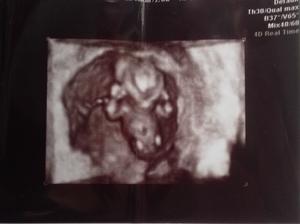

Ahoj děvčátka, tak jak je? Tak já se cítím dobře a myslím, že je to na dobré cestě zatím 😉 . Prsa mě bolí jako dooost, břicho chvílema jako na ms a mám dvy dny zácpu a to jsem dělala kachnu 😀 😀 . Tak doufám, že tam příští sobotu najdu // dálnice! Moc nám to všem přuju holky! Už si to zasloužíme! Tak doufám, že to nedělá utroš......

@lenik33 Krásná snůška vajíček 😀 určitě se oplodní všechny. Zítra si budeš volat, jak se jim daří? Tam bude šampionů několik 😉 . Já zkusím testnout zítra, je ji zle jak psovi. Dnes jsem koupila pět těhotenských testů, abych viděla, jestli sílí čárky, když budou. Věřím, že tam zítra už něco bude 😉 . Dám vědět a ty taky. Takže samý dobrý zprávy!

@pavlina1976 @zwalsh Moc krasne fotecky,jen tak dal 🙂 .